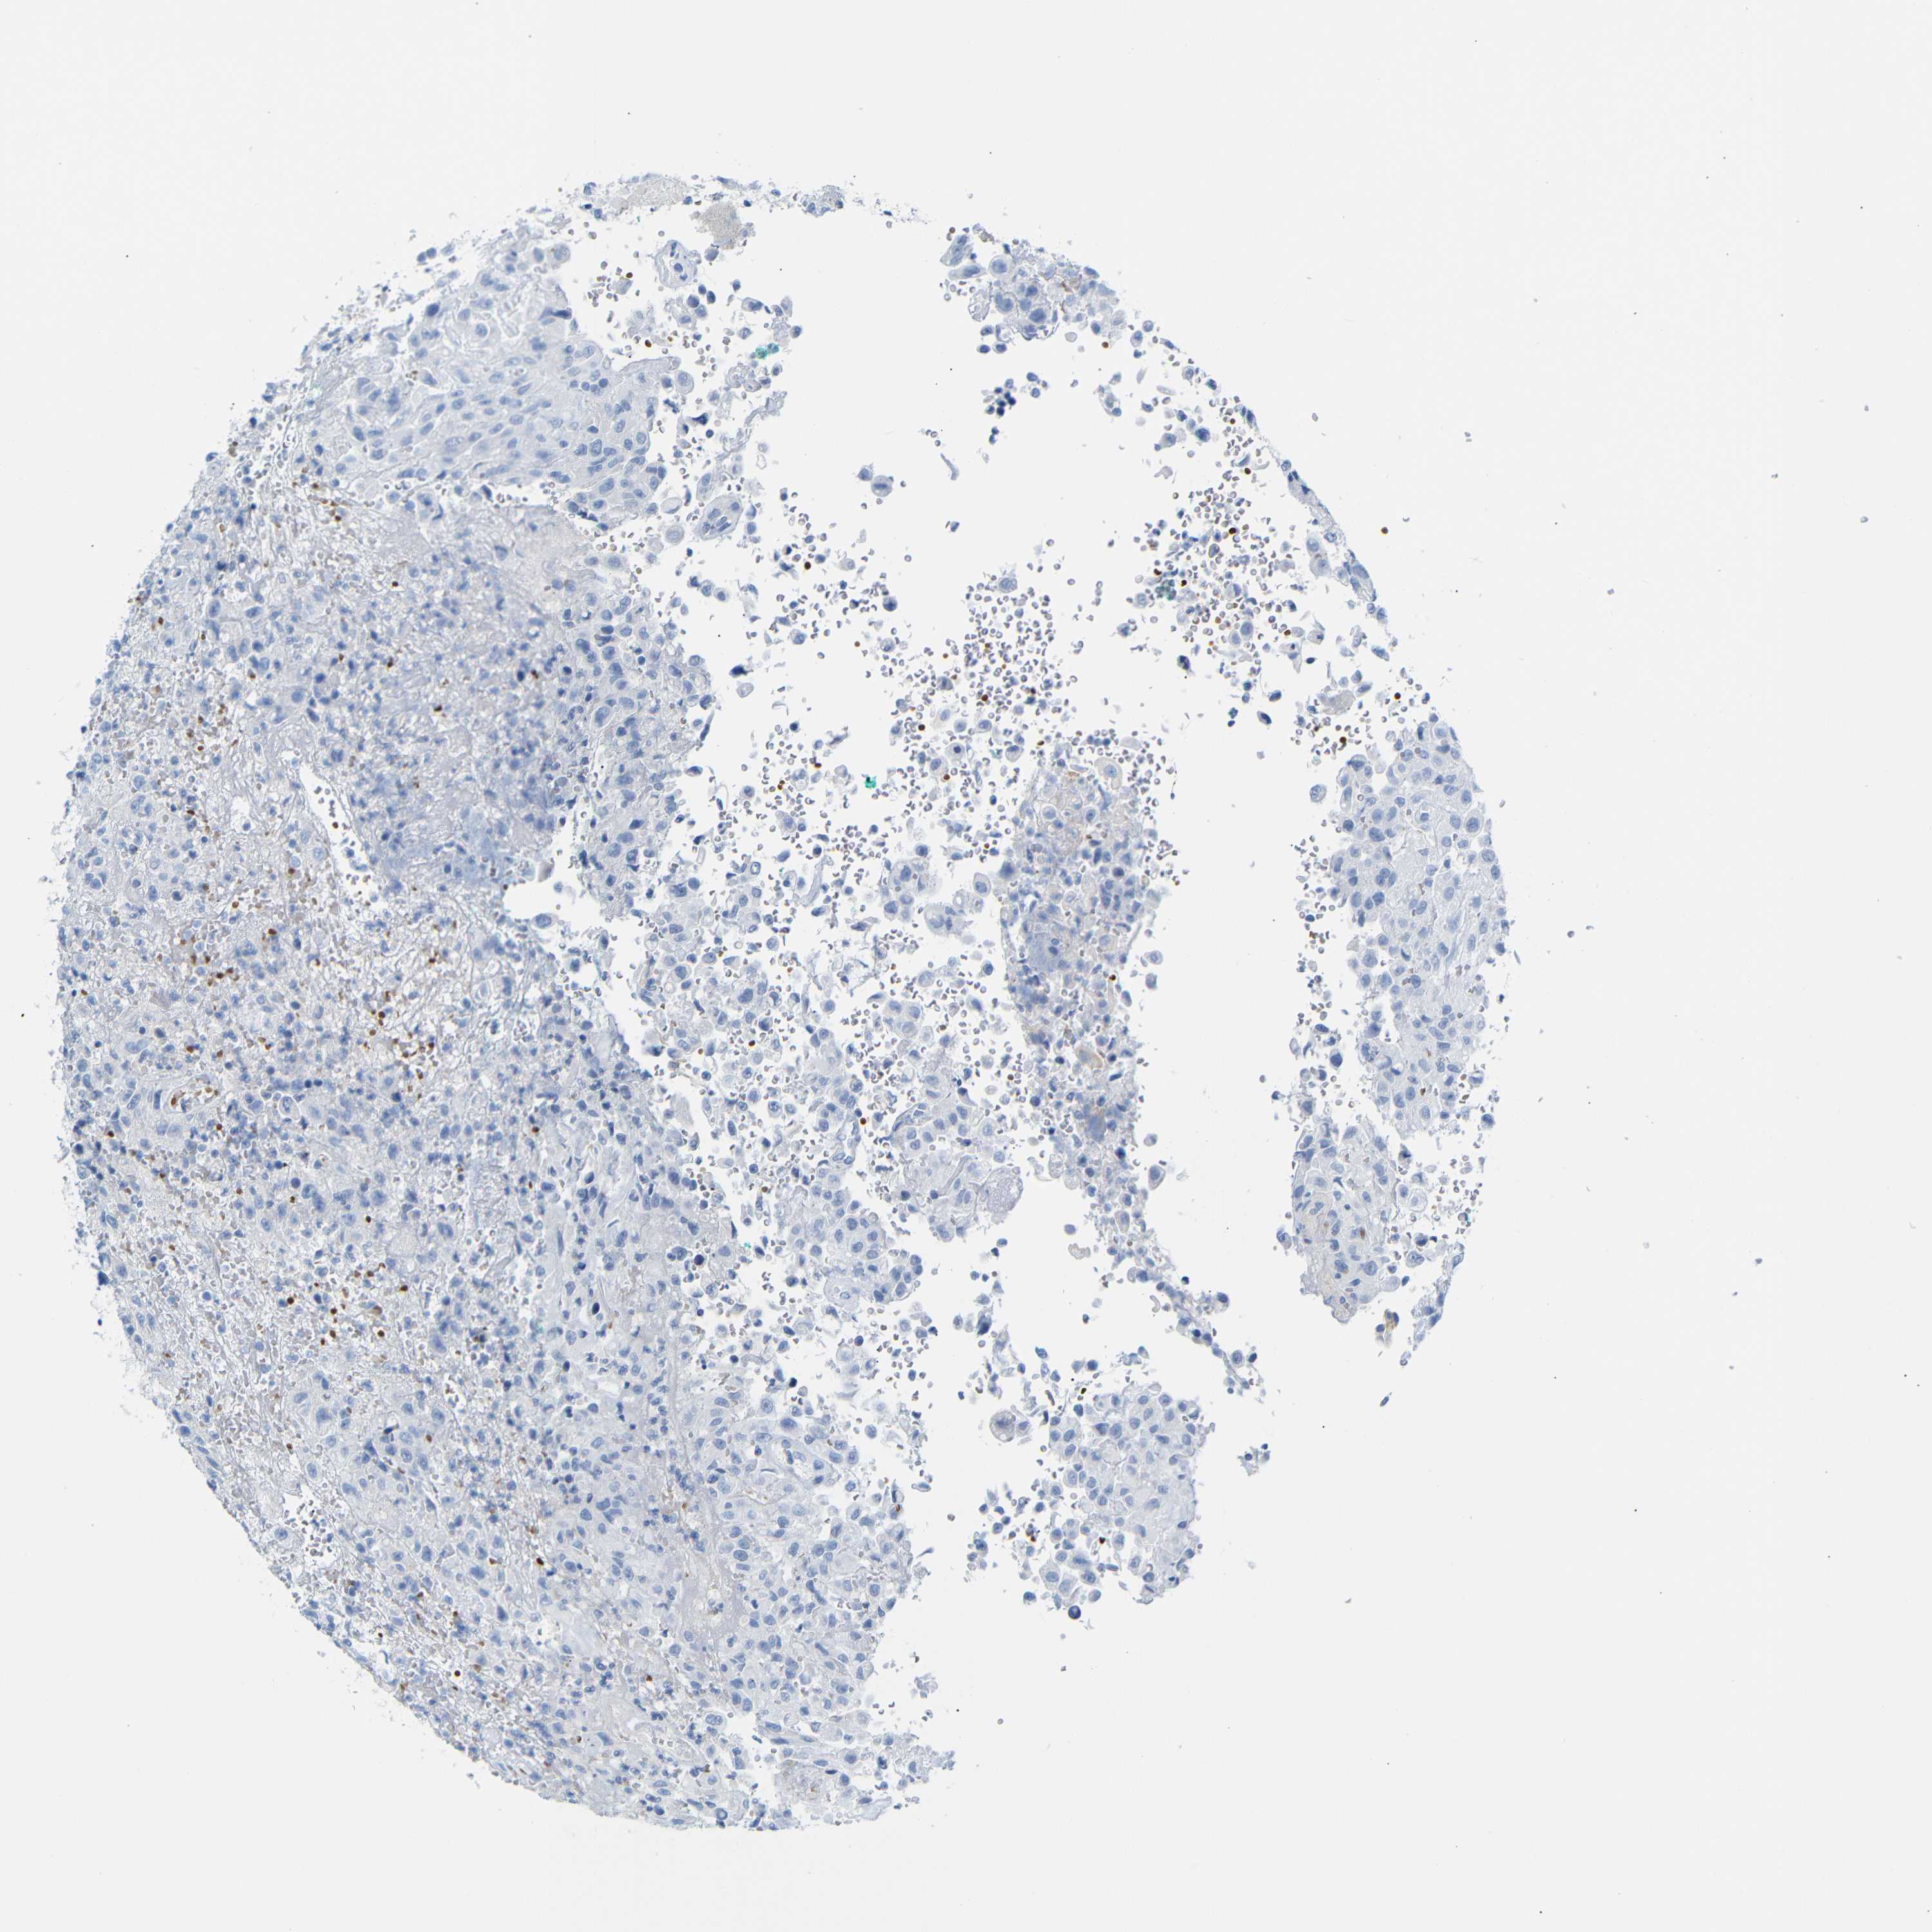

UROTHELIAL CANCER - Protein expressioni

A mouse-over function shows sample information and annotation data. Click on an image to view it in a full screen mode. Samples can be filtered based on level of antibody staining by selecting one or several of the following categories: high, medium, low and not detected. The assay and annotation is described here.

Note that samples used for immunohistochemistry by the Human Protein Atlas do not correspond to samples in the TCGA dataset.

Antibody stainingi

Antibody staining in the annotated cell types in the current human tissue is reported as not detected, low, medium, or high, based on conventional immunohistochemistry profiling in selected tissues. This score is based on the combination of the staining intensity and fraction of stained cells.

Each image is clickable and will lead to virtual microscopy that enables deeper exploration of all samples and also displays staining intensity scores, fraction scores and subcellular localization as well as patient and tissue information for each sample.

Antibody HPA011423

Staining

High

Medium

Low

Not detected

Intensity

Strong

Moderate

Weak

Negative

Quantity

>75%

75%-25%

<25%

None

Location

Nuclear

Cytoplasmic/membranous

Cytoplasmic/membranous,nuclear

Urothelial carcinoma, Low grade

Urothelial carcinoma, High grade